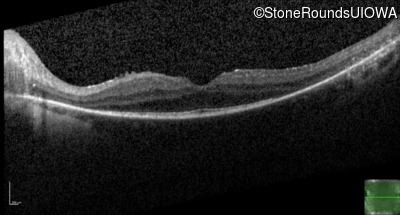

Age at visit: 39 years

OD OS